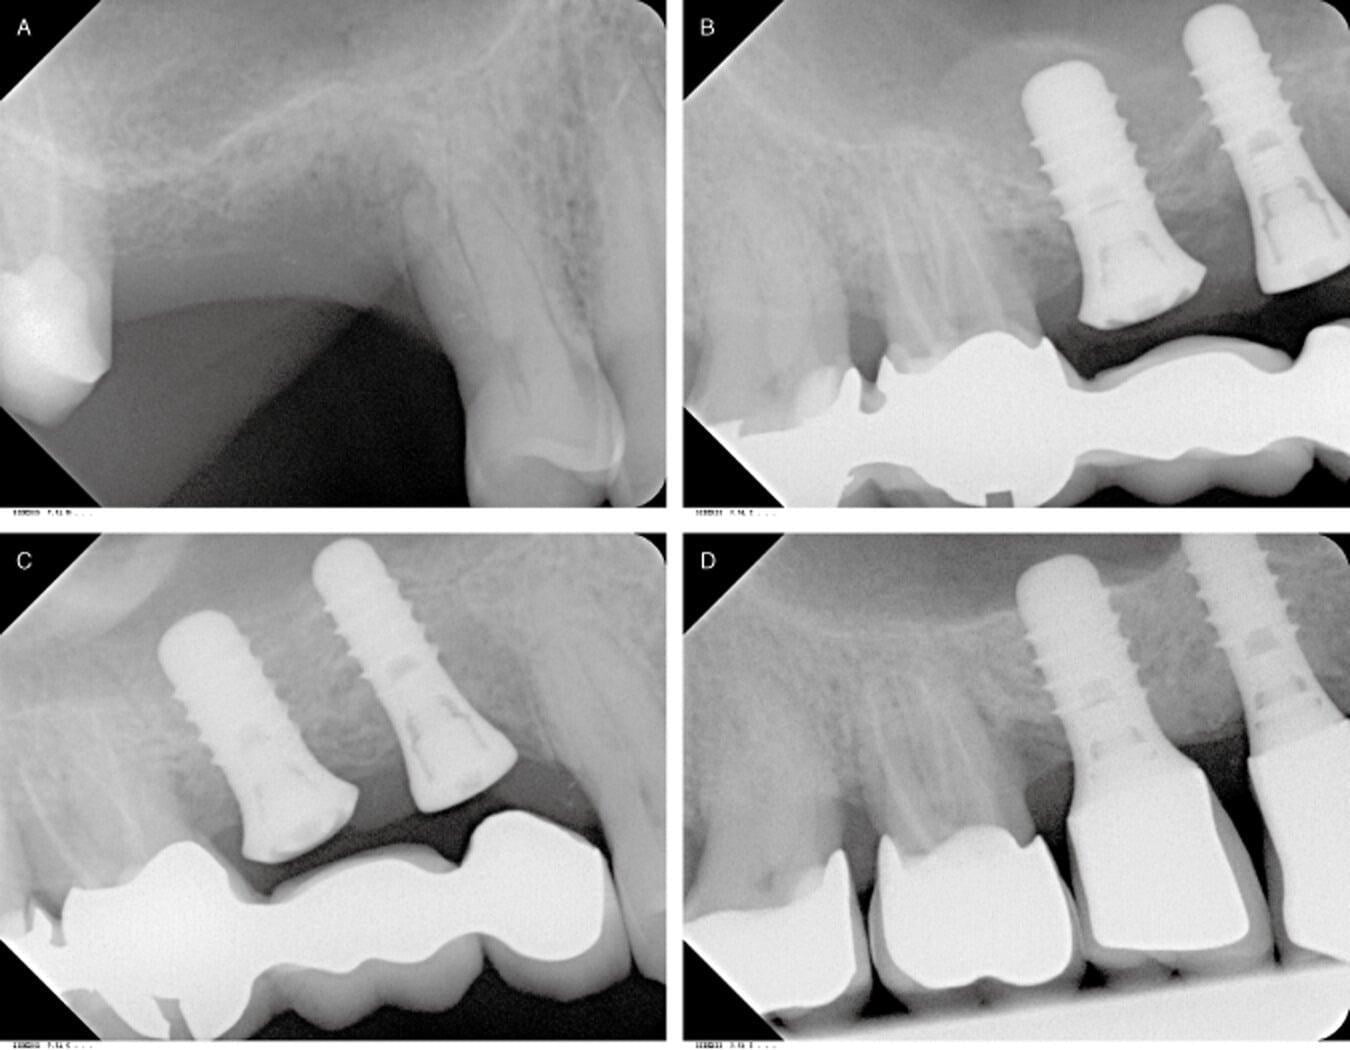

What Is A Dental Sinus Lift . Sinus lift surgery is a dental procedure used when the existing rear upper jaw (maxilla) bone is insufficient for dental implants. Learn more about the reasons, alternatives, and risks of sinus lift surgery. It is done to prepare for a dental implant when there is not enough bone to support it. A sinus lift, aka sinus augmentation, is a surgery that makes it easier to place dental implants. It involves “lifting” the sinus. A sinus lift (also known as a sinus augmentation or sinus floor elevation) is a surgical procedure that makes it possible to place dental implants. Some people need dental implants but don't have enough bone support necessary for implants because of bone loss. A sinus lift can help as it increases the amount of bone in the upper jaw by adding bone to the space between your molars and premolars. A sinus lift is an oral procedure to extend the upper jawbone into the maxilla sinus cavity with a bone graft. Dental implants fuse with the jaw bone in a process. A sinus augmentation is performed when a patient has insufficient bone in their upper jaw to support a dental implant. A sinus lift, also known as sinus augmentation or sinus elevation, is a surgical procedure that adds bone to the maxillary sinus. To reinforce this area, oral surgeons graft harvested or synthetic bone into a space created by lifting the